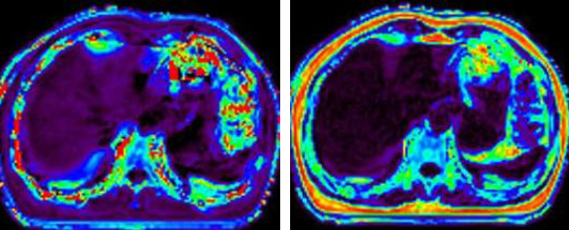

在现代医学影像技术的浪潮中,磁共振成像(MRI)以无辐射、高软组织分辨力、多参数成像的独特优势,成为疾病诊断的核心工具之一。而磁共振3D扫描技术,更以其立体成像的优势受到关注——它能为人体内部病变区域构建清晰的三维图像,让病灶细节无所遁形。如今,玉溪市中山医院医学影像科在中山大学附属第一医院派驻专家张朝晖教授的领衔下,已熟练开展多部位磁共振3D扫描技术,将这项前沿技术转化为精准诊断与治疗的“硬核支撑”...